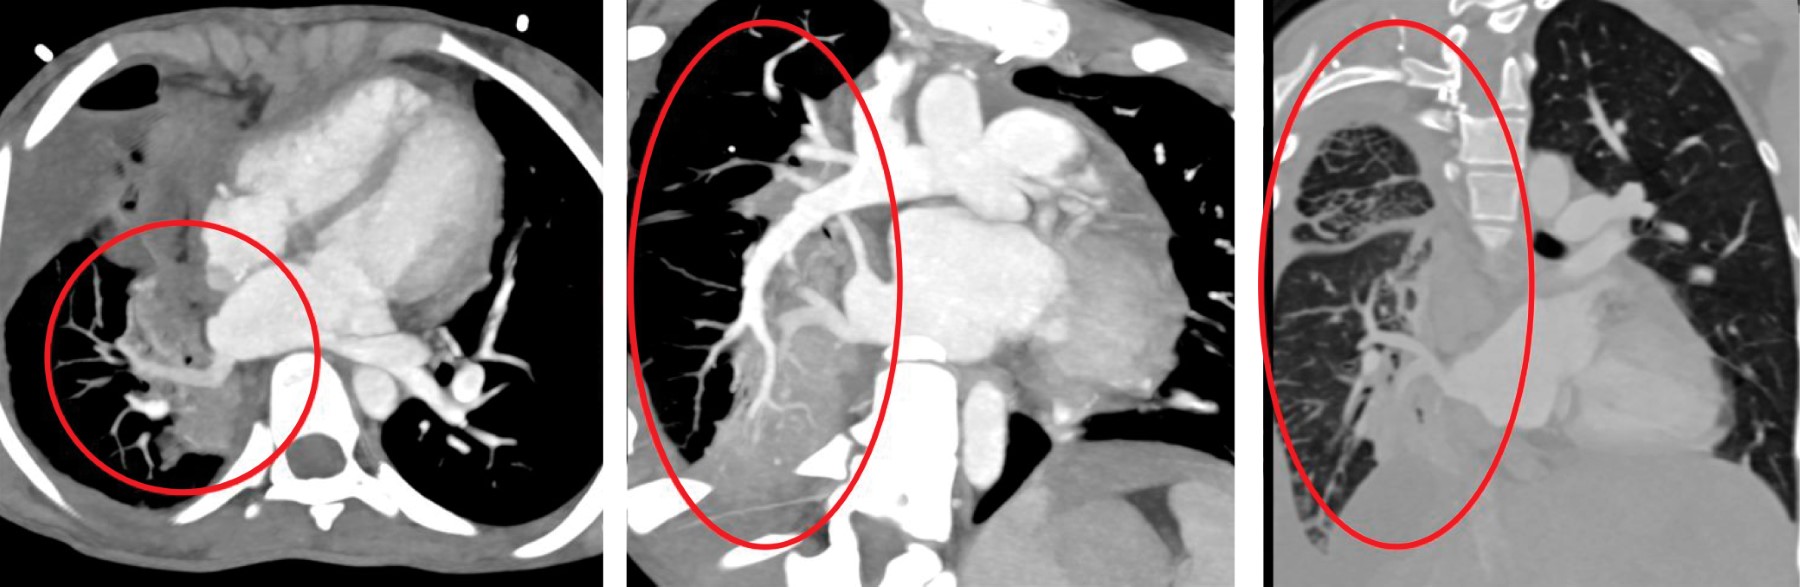

At the time of the echocardiogram, it was observed obstruction in the right PV with a mean gradient of 11 mmHg and a mean gradient of 9 mmHg in the left PV. Pulmonary arterial hypertension and appropriate biventricular systolic function were noted. A contrast-enhanced computed tomography revealed a significant reduction in the right lung volume, dorsal atelectasis, and a right pleural effusion. A decision was made to perform catheterization, during which a reduction in the caliber of the left PV was found upon arrival at the coronary sinus with an obstructive gradient of 9 mmHg. The proximal portion of the right upper PV was also retrograde, with amputation of both veins upon arrival at the left atrium. The PV cannot be successfully opened, leading to the termination of the procedure.

Figure 3